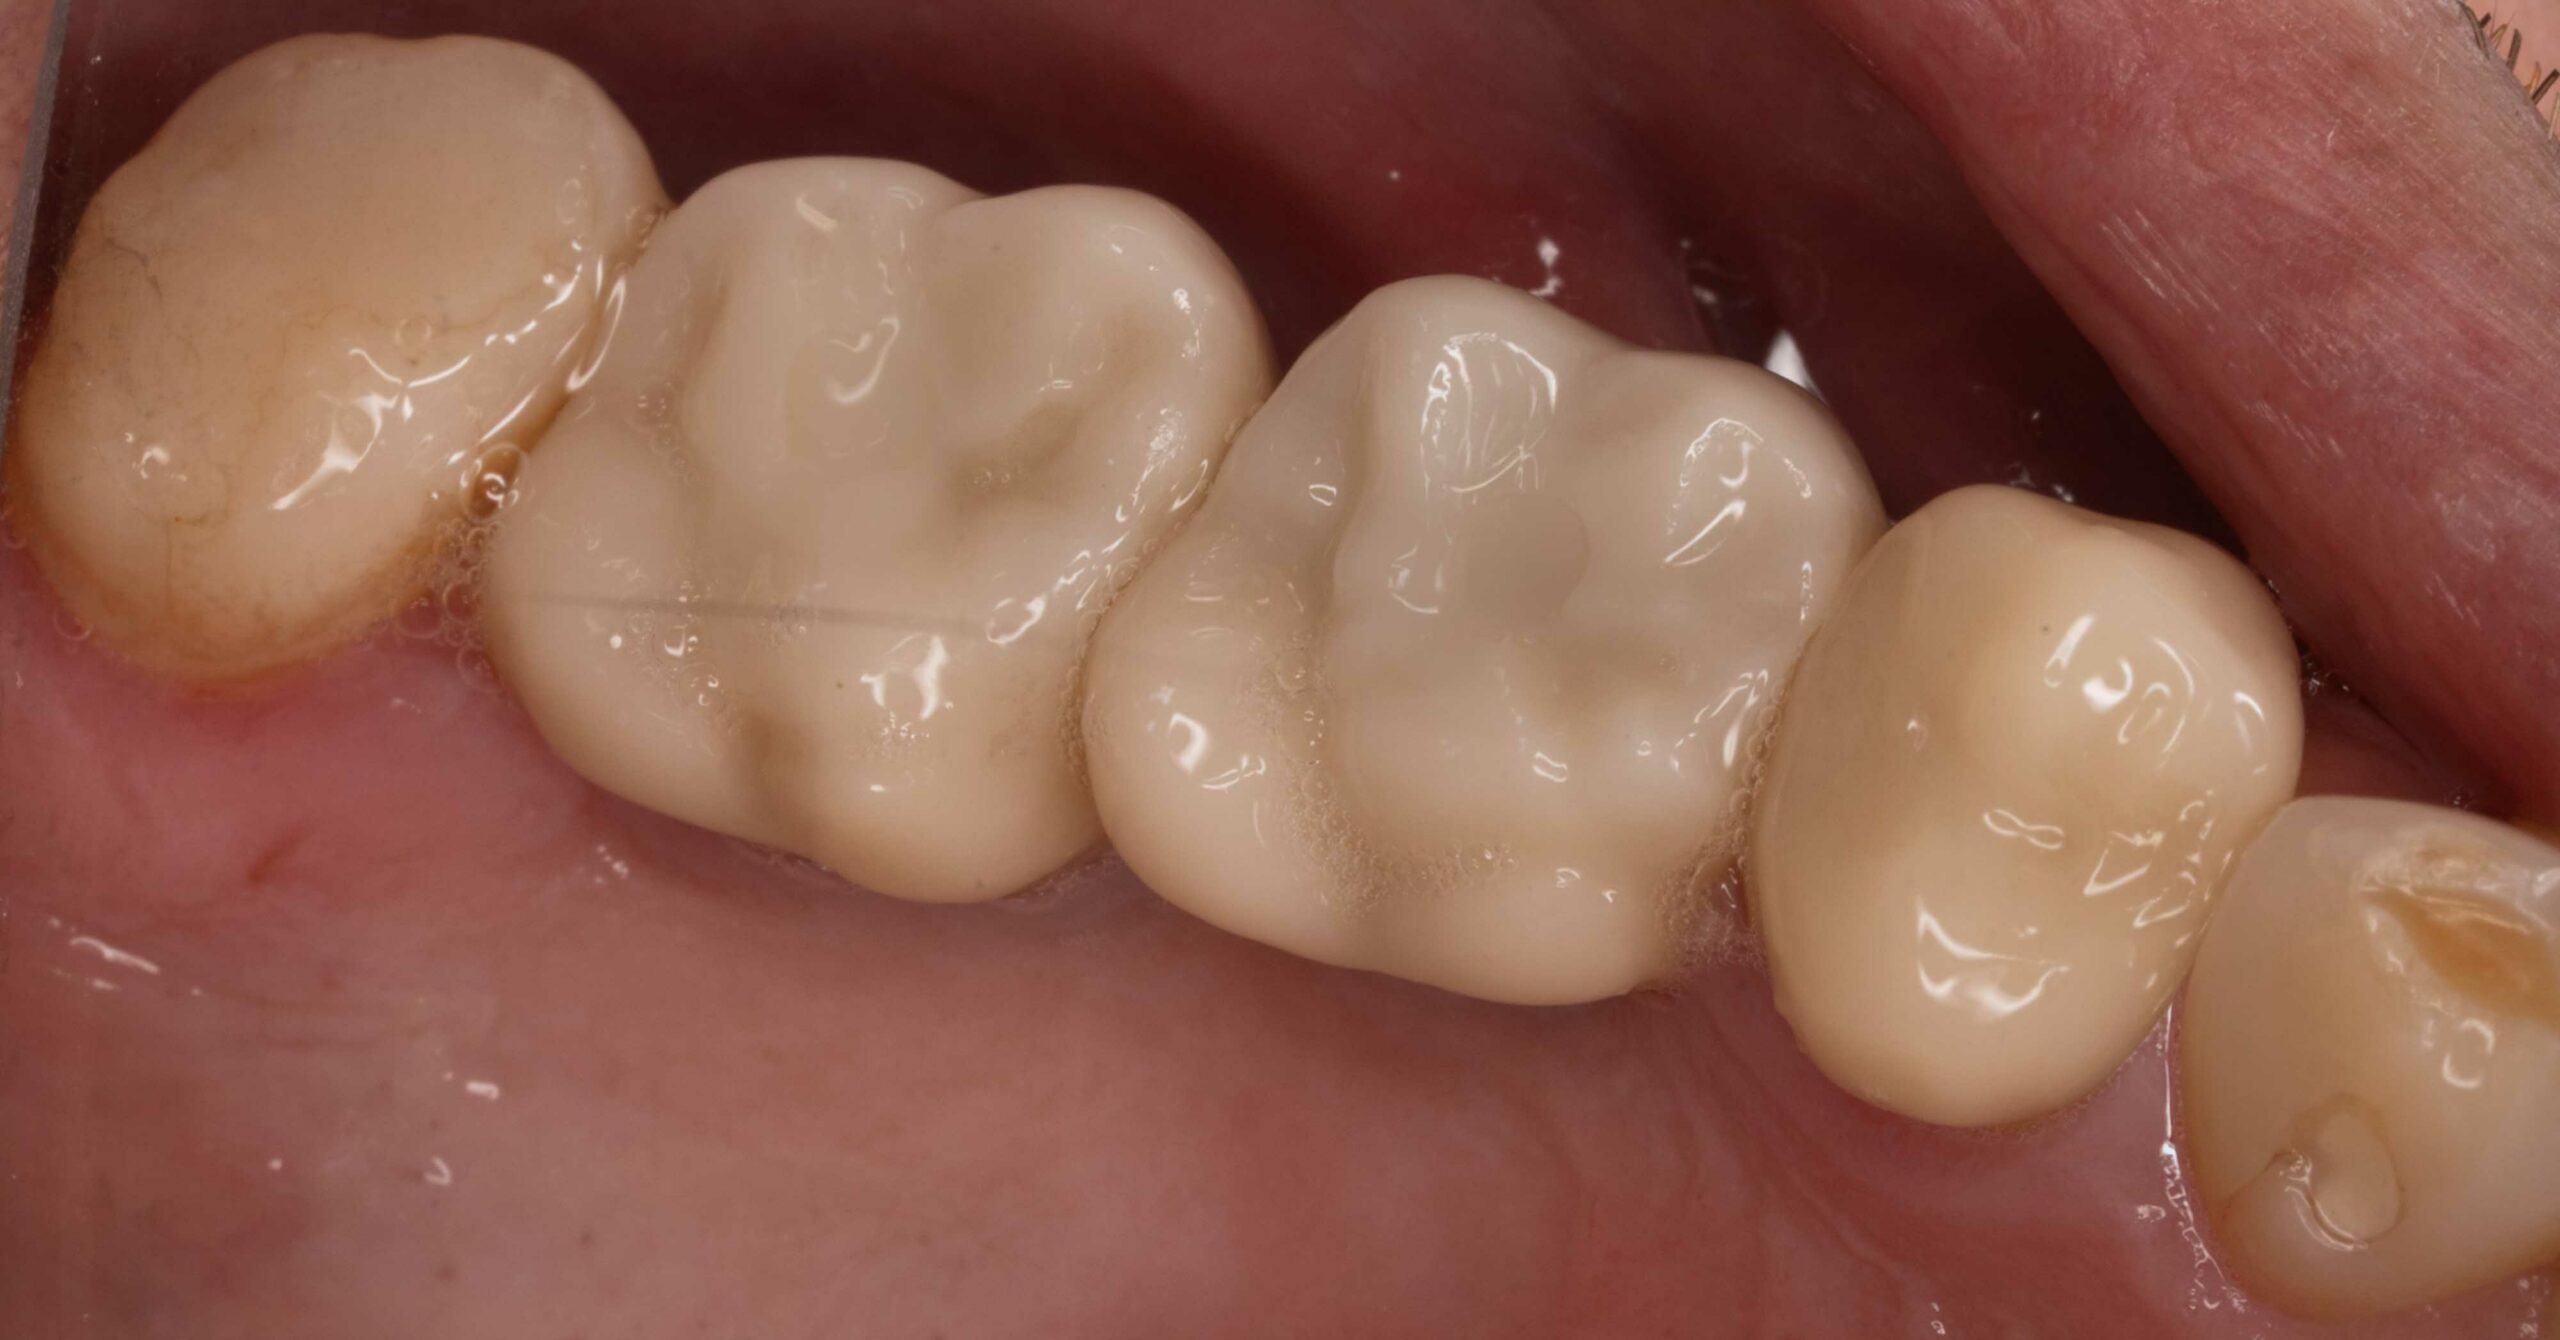

Wymiana mostów

Pacjentka zgłosiła się w celu wymiany mostów zaburzających proporcje uśmiechu.

U Pacjentki wykonano:

- usunięcie poprzedniej odbudowy

- mosty ceramiczne odtwarzające prawidłową ilość i proporcję zębów

Leczenie przeprowadził lek. dent. Kamil Kikowicz